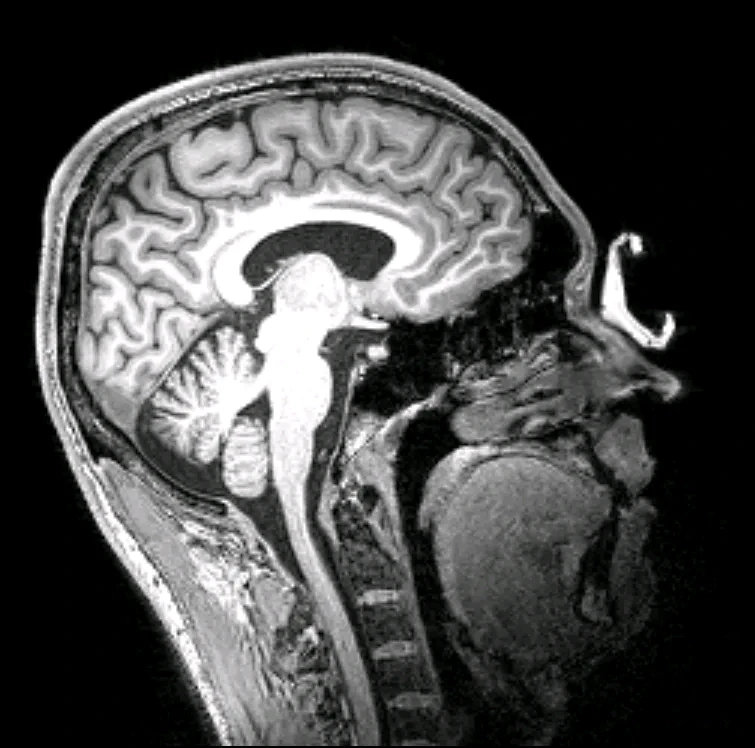

MR scan in sagittal plane of my brain during research study.